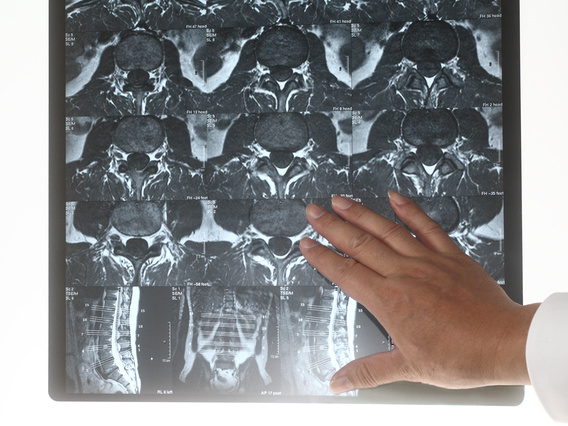

MRI検査について

スポーツ選手のMRI検査

MRI検査はどこの病院で受けても同じではありません。

MRI検査は病院によって、【テスラ(磁場強度)】が異なります。

テスラとは、デジカメの画素数のようなもので、数値が高い機種ほど高解像度となります(1.5 テスラ以上が必要です)。

MRIの検査方法(MRIの設定)は難しく、専属のスタッフが常駐し、代表する専属の医師や責任者の存在が不可欠です。

MRIの画像から、診断をしていくことを専門としている医師が「画像診断医」と呼ばれます。画像診断医の居る病院で受けましょう。